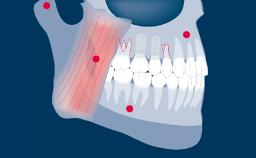

Implant-Supported Provisional Prosthesis

When providing a patient with an implant-supported rehabilitation, clinicians must decide whether to fabricate a provisional prosthesis or go directly to the definitive prosthesis.

Several factors play a role in making the correct decision. These involve the location of the implant anterior or posterior site, the number of implants, the need to shape tissue, as is often seen with adjacent implants in the anterior area, and the need for occlusal support.

The patient’s wishes may also play a role in this decision. This module will highlight the indications, materials and techniques for fabrication and utilization of an implant-supported provisional prosthesis.